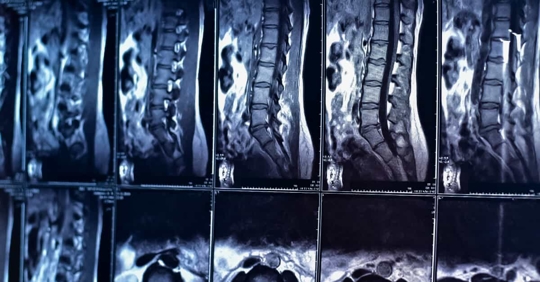

spinal cord injury

Spinal Cord Injuries

Spinal cord injuries (SCIs) are life-changing events, typically resulting from accidents, falls, or trauma. These injuries can lead to varying degrees of paralysis, impacting an individual's mobility and overall quality of life. While some SCIs cause temporary limitations, others result in permanent disabilities. Treatment and rehabilitation are essential to help manage the effects of SCIs. Advanced medical therapies and assistive devices have improved the outlook for those with spinal cord injuries, offering hope for enhanced independence and functional recovery. However, prevention remains the best approach—promoting safety measures and responsible behavior to reduce the risk of these devastating injuries.

Top causes of spinal cord injuries include:

• Motor Vehicle Accidents: Collisions often result in spinal cord injuries, including whiplash.

• Falls: Falling from heights or slipping and falling can lead to these injuries.

• Sports Injuries: High-impact sports like football and gymnastics carry a risk of spinal cord injuries.

• Medical Malpractice: Surgical errors or improper medical procedures can also cause spinal cord damage.